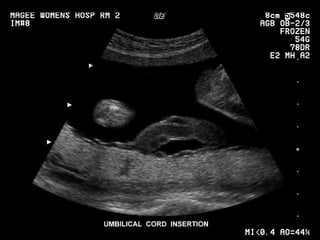

Cordão umbilical Inserção placentária. Inserção extraplacentária (velamentosa). Comprimento (40 a 60 cm). Geléia de Wharton. Artérias (2), Veia (1).

Cordão umbilical Inserçãoplacentária. Inserção extraplacentária (velamentosa). Comprimento (40 a 60 cm). Geléia de Wharton. Artérias (2), Veia (1).